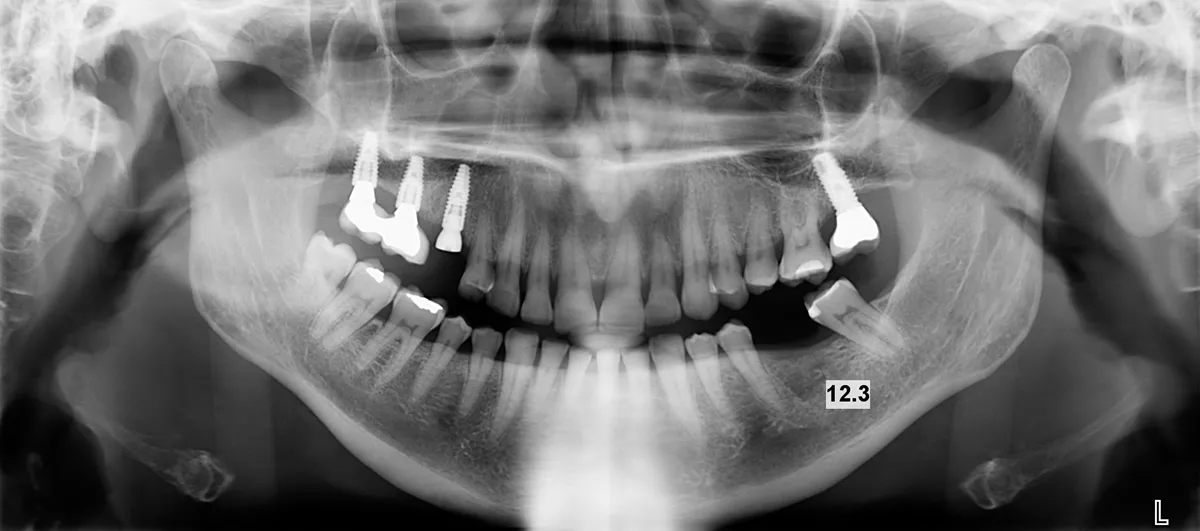

Two months later, a panoramic x-ray showed an excellent situation for the BLT implant and correct healing of the #36 area (Fig. 1).

fig. 1